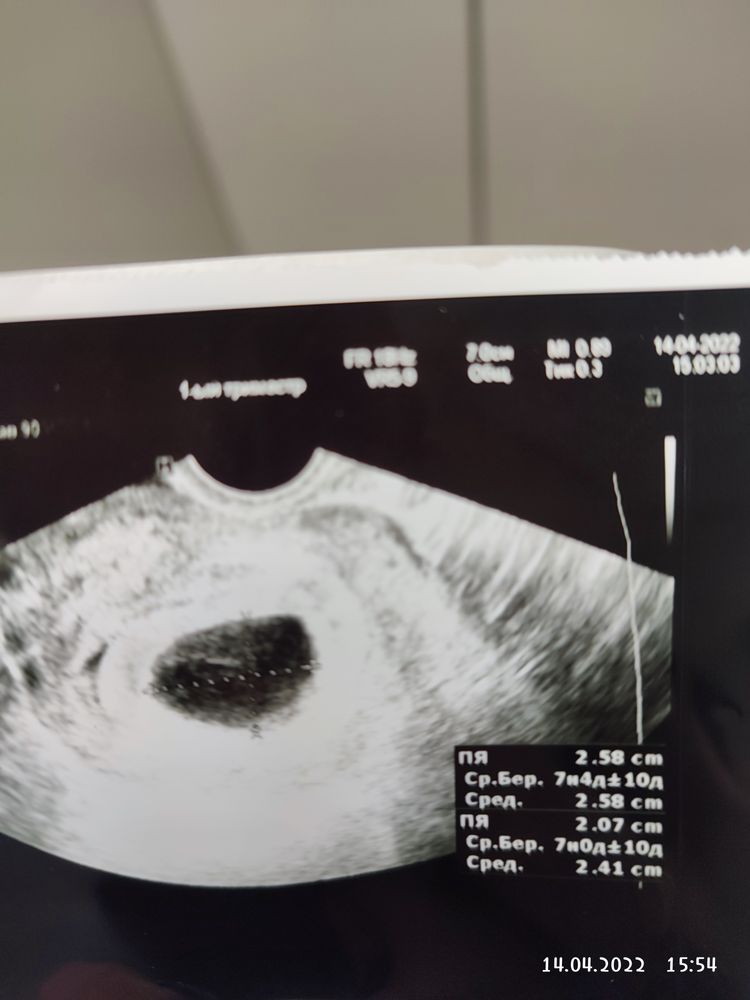

Чуда не случилось, эмбриончика нет 😭

Ну даже жм нет🤷‍♀️ переделайте конечно...но готовьтесь к любому исходу

Кали Юга, спасибо за поддержку.Муж говорит, оборудование-говно, простите) Видишь,говорит,там полоску,вот это только он появляется.

Katerina , полоску я эту тоже заметила, но где жм то тогда? Нельзя конечно отметать и говноаппарат)

Кали Юга, я была неделю назад, врач сказала ЖМ пока слабо визуализируется, эмбриончика нет, сегодня она позвала второго врача, та говорит,он у тебя уж разложился почти...Не могу понять как так может быть, неделю назад нет, а сегодня разложился 🤷Я была в таком шоке,что ничего не спросила толком

Katerina , разложиться действительно мог, т.к там микроразмеры же